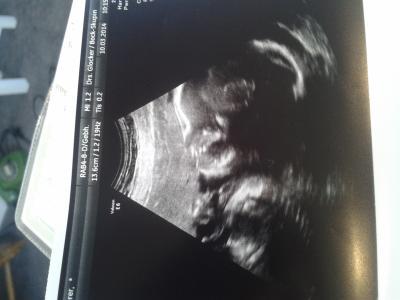

Der zuckertest war garnicht so schlimm. Man konnte es wirklich so einigermaßen trinken. Unser mäuschen wiegt ca 625 Gramm.GGröße hat die Ärztin nur gesagt ist zeitgerecht. Mein mumu ist trotz 9 Wochen Kontraktionen weiter stabil. Sogar heute gemessen 5, 7 cm. Die Ergebnisse vom Zucker test bekomme ich morgen abend. Bin gespannt. Und zum ersten Mal muss ich 4 Wochen warten zur vorsorge termin mit dann auch ctg.Allerdings habe ich in einer Woche meinen 3d termin. Darauf freue ich mich sehr. Und verkürzt die Wartezeit.